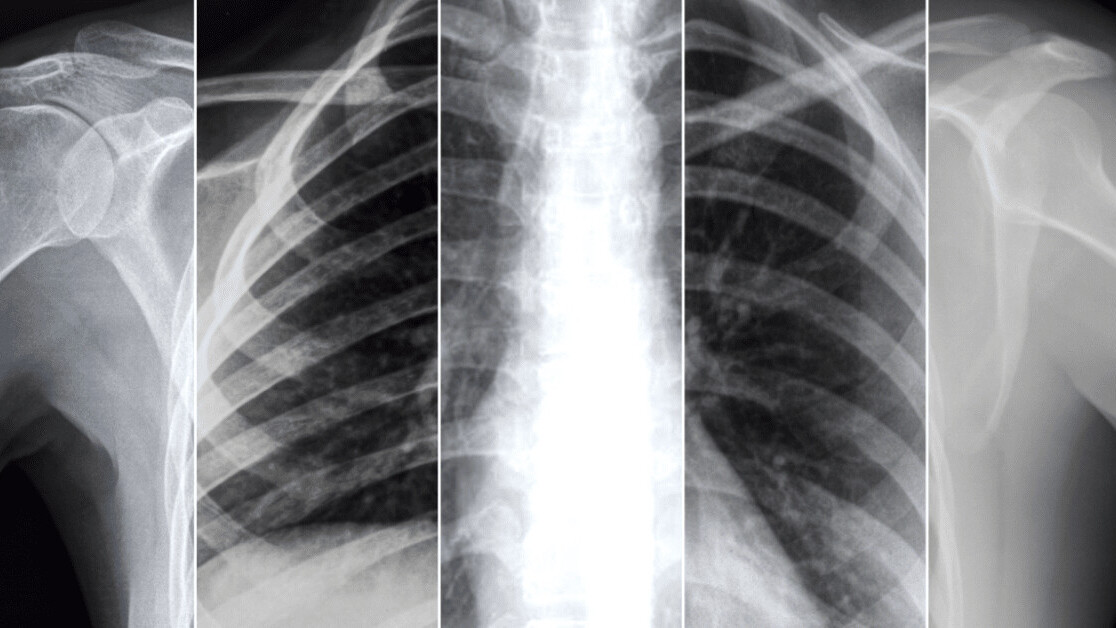

Researchers from Facebook and NYU Langone Health have created AI models that scan X-rays to predict how a COVID-19 patient’s condition will develop.

The team says that their system can forecast whether a patient may need more intensive care resources up to four days in advance. They believe hospitals could use it to anticipate demand for resources and avoid sending at-risk patients home too early.

Their approach differs from most previous attempts to predict COVID-19 deterioration by applying machine learning techniques to X-rays.

They first pre-trained their system on two public X-ray datasets, using a self-supervised learning technique called Momentum Contrast (MoCO). This allowed them to use a large quantity of non-COVID X-ray data to train their neural network to extract information from the images.

They used the pre-trained model to build classifiers that predict if a COVID-19 patient’s condition will likely worsen. They then fine-tuned the model with an extended version of the NYU COVID-19 dataset.

This smaller dataset set of around 27,000 X-ray images from 5,000 patients was given labels indicating whether the patient’s condition deteriorated within 24, 48, 72, or 96 hours of the scan.

The team built one classifier that predicts patient deterioration based on a single X-ray. Another makes its forecasts using a sequence of X-rays, by aggregating the image features through a Transformer model. A third model estimates how much supplemental oxygen patients might need by analyzing one X-ray.

They say using a sequence of X-rays is particularly valuable, as they’re more accurate for long-term predictions. This approach also accounts for the evolution of infections over time.